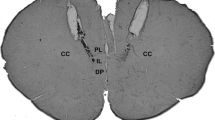

Figure 2 shows a photomicrograph of a coronal section of rat brain implanted with bilateral guide cannulae into the DH and diagrammatic representations of injection sites of drugs and vehicles administered into the DH or in the surrounding structures of the DH.

Photomicrograph of a coronal section of the hippocampus and the injection sites within the DH. Diagrammatic representations with the injection sites of the vehicle (gray circles), drugs into the DH (black circles), and in surrounding structures (white circles) of the DH. Coordinates according to the Rat Brain Atlas of Paxinos and Watson (1997)